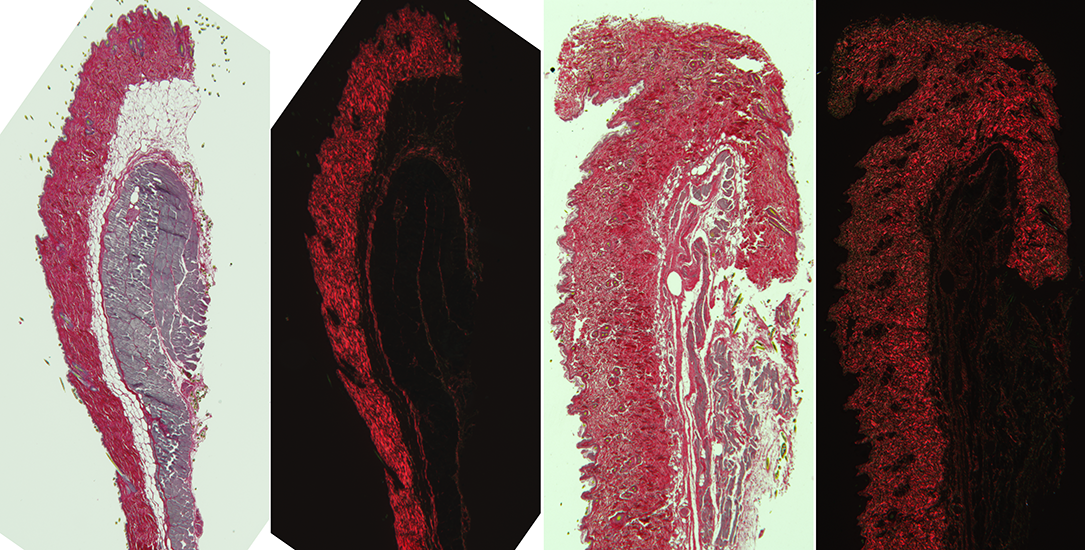

Polarized light microscopy with AxioObserver.

LEFT: Brightfield image of chromogranic stained skin (prepared by Histology Core).

RIGHT: Crossed polarization image of same sample. Note that only the collagen depolarizes the light and that direction of collagen can be discerned in the images. (This can also be done with unstained tissue and with fluorescently stained tissue.)